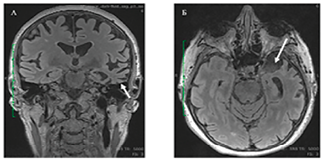

смeшанная ППА |

Сочетание признаков аППА и лППА. |

||